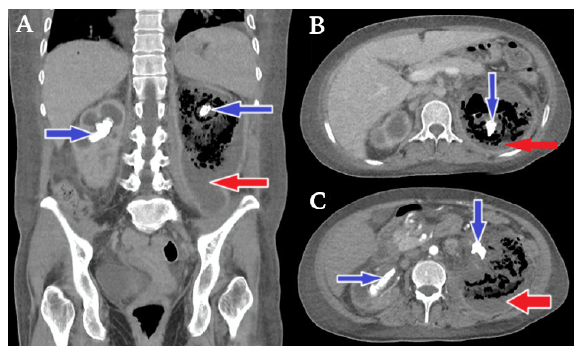

On the fifth day of admission, due to the persistence of intermittent fever (Figure 1), hypoactive delirium and hypoglycemia, as well as the presence of oliguria with purulent urine and the need for vasopressors, a contrast computed tomography urogram was performed (Figure 2), which showed the following: 1) right kidney of 108x54x43mm with staghorn calculi of 46x41x16mm inside and dilatation of the pyelocaliceal system of up to 23mm.; 2) left renal fossa of 236x87x88mm with loss of renal morphology due to the presence of gas and air-fluid levels (destruction of the renal parenchyma); 3) scarce contrast-enhancing parenchymal areas in the collecting and intraparenchymal system, and 4) presence of staghorn calculi in the upper pole (29x14mm), interpolar region (23x17mm) and proximal ureteropelvic junction (24x15mm). Based on these findings compatible with emphysematous pyelonephritis and coraliform lithiasis, it was decided to continue with the antibiotic therapy already established.

Contrast computed tomography urogram.

Figure 2: Contrast computed tomography urogram.

→ Perirenal collection mixed with liquefied necrotic purulent fluid settled in the fundus with air in the upper part giving rise to renal air-fluid levels, a finding suggestive of class 3B emphysematous pyelonephritis in the left kidney according to Huang's classification.

→ Bilateral staghorn calculi with characteristics of coralliform lithiasis.

Source: Own elaboration.